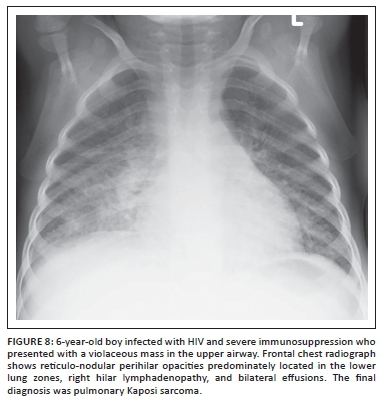

Pediatric patients with HIV may also present with rare pulmonary Kaposi sarcoma, which is characterised by the perihilar airspace and reticular opacification predominately involving the lower lung zone in addition to hilar lymphadenopathy and often large pleural effusion (Figure 8).10